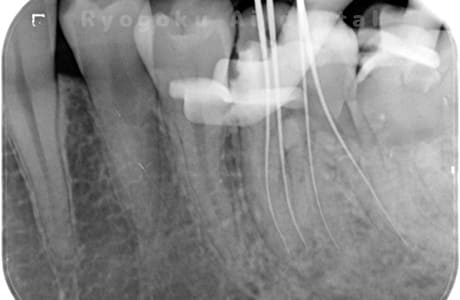

噛むと痛みが出る、とのことで来院した患者様です。他院での根管治療を終えてましたが、根尖病変を認めるため、マイクロエンドを行いました。